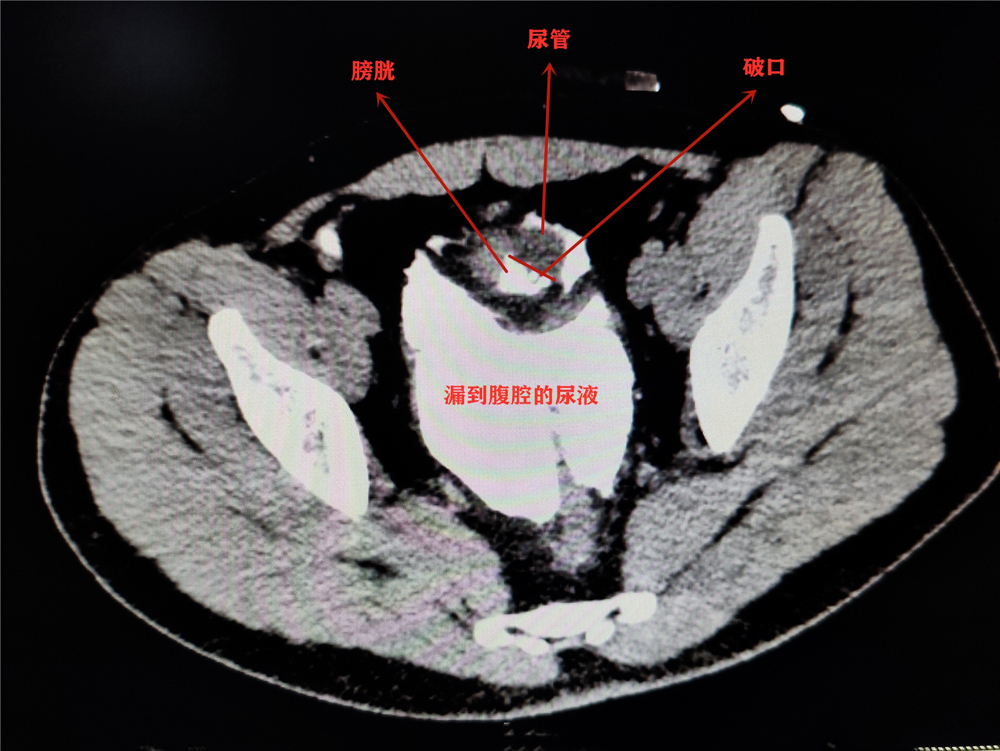

在病床上的小李说起这两天的经历,也是有些哭笑不得。7月25日晚上,小李和朋友相约聚会吃冷淡杯、喝啤酒,期间没上过一次厕所。聚会结束后,站起身的小李脚下一滑摔了一跤,刚好肚子撞在了桌角上,这一撞,让他感觉疼痛难耐,随即被送到了就近的医院。医生先是给他安装了尿管紧急处置,经过进一步检查发现其腹腔内已经有尿液,说明是膀胱发生了破裂。

辗转几家医院,小李在26日晚上被送到了成都市第三人民医院。该院泌尿外科副主任医师袁仁斌博士说,小李膀胱有一个4*3cm的破洞,尿管也顺着洞“跑”到了腹腔内,因为尿液在腹腔内蓄积了很长时间,已经引发了比较严重的腹膜感染,“如果再不及时手术,可能生命都会受到威胁。”